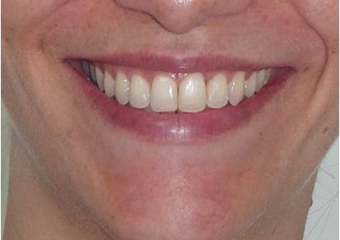

Sorriso incial

Sorriso final